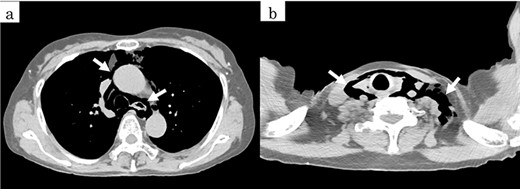

On chest and abdominal CT, free gas was observed in the entire abdominal cavity (Fig. 1a), and extensive emphysema was also observed in the retroperitoneum (Fig. 1b). In addition, it was observed from the mediastinum to both sides of the necks (Fig. 2).

Preoperative CT showed (a) pneumoperitoneum (arrows) and (b) a massive pneumoretroperitoneum (arrows).